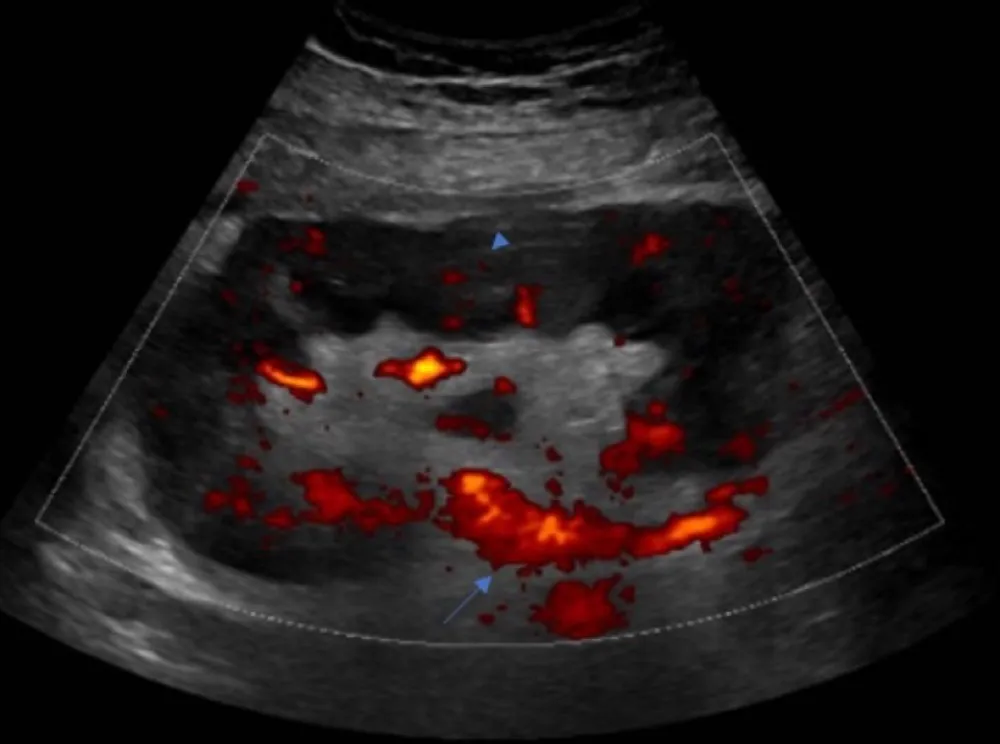

Uma causa incomum de hematúria glomerular intermitente!